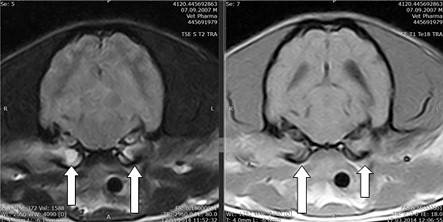

Средний отит устанавливается на основе клинических симптомов, состояния барабанной перепонки и методов визуальной диагностики. При остром течении заболевания на рентгеновских снимках могут наблюдаться такие изменения, как затрудненная видимость горизонтального слухового прохода из-за отека, тогда как при хроническом процессе фиксируется линейное обызвествление тканей наружного уха. В среднем ухе изменения могут отсутствовать или проявляться в виде лизиса стенок, утолщения барабанного пузыря, склероза или увеличения рентгеноконтрастности просвета. Часто эти изменения остаются незамеченными, однако на качественных рентгеновских снимках, где видны структуры внутреннего уха, можно выявить признаки склероза или размытые контуры лабиринта. Важно помнить, что череп имеет двустороннюю симметрию, поэтому потеря симметрии может указывать на наличие заболевания. Компьютерная томография (КТ) является более точным и надежным методом диагностики среднего отита по сравнению с рентгеном, хотя при легкой форме оба метода менее эффективны, чем при более тяжелых случаях. Магнитно-резонансная томография (МРТ), если она доступна, лучше подходит для визуализации мягкотканевых структур или новообразований, в то время как КТ более эффективно выявляет изменения в костных структурах.

Рис. 1 Собака породы грифон. Содержимое барабанных полостей заполнено экссудатом, наружный слуховой проход не содержит воздуха. Рис. 2 Французский бульдог с симптомами поражения вестибулярного аппарата.

Справа видно поражение барабанной полости, утолщение костной ткани барабанной полости (толстая стрелка) по сравнению с левой стороной (тонкая стрелка). Вход в барабанную полость практически отсутствует (фигурная стрелка).

Рис. 3 Та же собака. Воспалительный экссудат, костные структуры визуализируются слабо.

Однако последовательность программ FLAIR, Т2, Т1 и контрастирование позволяют провести дифференциальную диагностику между воспалением и новообразованием, а также оценить наличие воспалительного процесса в нервной системе (рис. 4).

А. Воспалительный процесс в барабанной полости вызвал воспаление оболочек головного мозга (стрелка). В. Накопление контраста указывает на воспалительный процесс (фигурная стрелка), необходимо сравнить рисунки Б и В. Г. Отек головного мозга воспалительного происхождения.